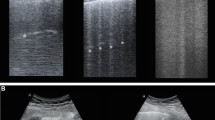

Representative lung CT and corresponding LUS images in ventral, intermediate and dorsal lung regions at early and late stages of ARDS in two opposite cases of aeration improvement or worsening are shown in Fig. 1 (panel A and B). Absolute total and regional LUS score and Pair, Pnorm, Ppoor and Pnot values at Early and Late time points are described in Table 1S.

According to LUS image characteristics each field was graded as: N (normal aeration): lung sliding/lung pulse with A lines or less than two B lines for intercostal space; B1 (moderate loss of lung aeration): multiple spaced B-lines, more or equal than 3 for each space; B2 (severe loss of lung aeration): multiple coalescent B lines with or without subpleural consolidations; C (consolidation): presence of a tissue pattern with or without air bronchograms [13,14,15,16,17], where N = 0, B1 = 1, B2 = 2, C = 3 [15]. LUS score was directly obtained (real time) and reported by the observer for each field in a dedicated case report form.